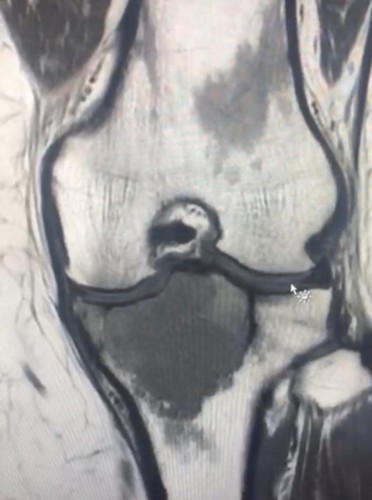

استئصال ورم في عظمة ساق مريضة في مستشفى المدينة المنورة الاثنين 1442/4/1 هـ الموافق 2020/11/16 م يواصل الفريق الطبي المختص في جراحة أورام العظام والعضلات في مستشفى المدينة المنورة إجراء العمليات الجراحية التخصصية في هذا المجال ، حيث نجح الفريق مؤخراً في استئصال ورم في أعلى عظمة الساق اليسرى لمريضة. يذكر أن المستشفى تبلغ سعته السريرية 200 سرير، وخلال الأشهر الثلاثة الماضية ،شملت خدماته المقدمة للمراجعين 256 تصويرا للقلب و7369 مراجعاً للعيادات الخارجية و188468 فحصاً مخبرياً و8034 خدمة للأشعة .